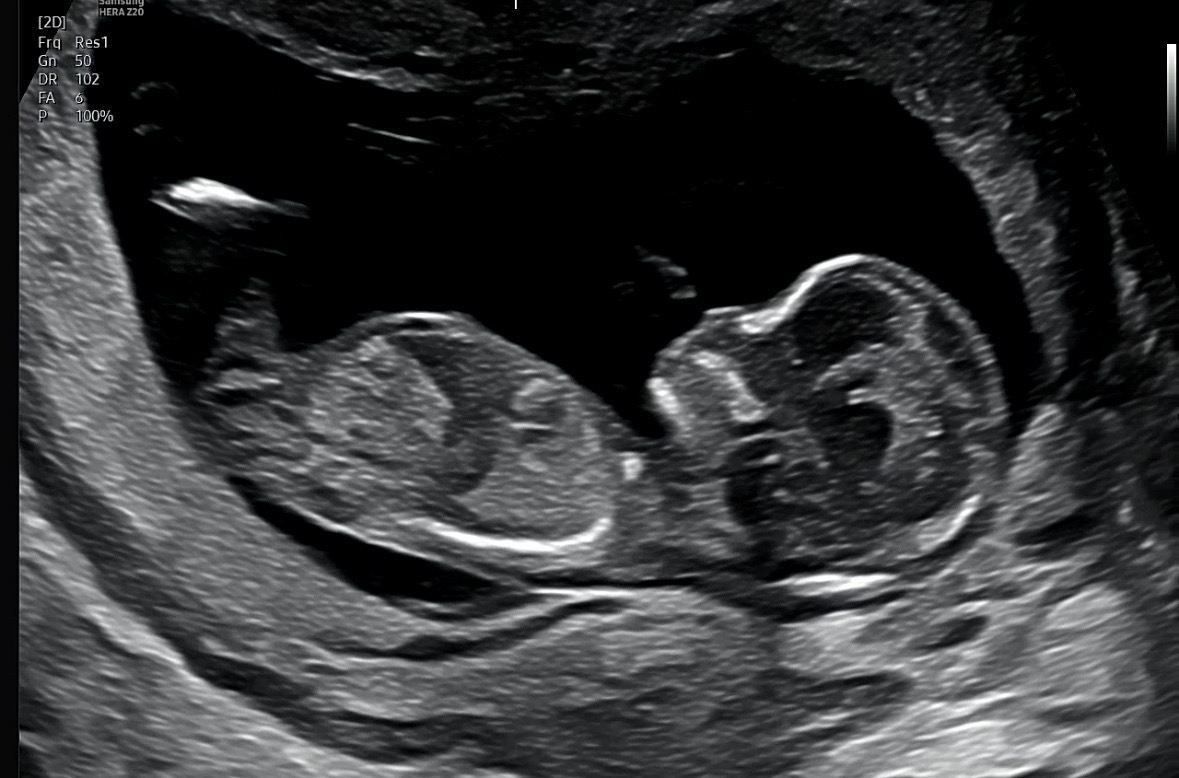

각도법 고수님들 도와주세요 성별이 뭘까요?

잘 안보이는거 같아요 ㅠㅠ